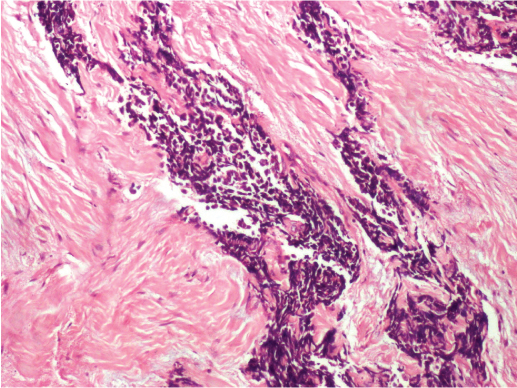

A 46-year-old male patient presented with complaint of painful bleeding and lumps in anal region since 3 months. He had undergone haemorrhoidectomy one year back. He didn’t have any other co-morbid conditions. There was no history of smoking. Per rectal examination couldn’t be done without anaesthesia since he had sphincter spasm. On evaluation under anaesthesia, the patient had a freely mobile, friable growth about 2 cm from the anal verge along posterior and the lateral wall. A biopsy was taken and the histopathological examination revealed small malignant cells with hyperchromatic nuclei and scanty cytoplasm with tumour invading the fibro-collagenous tissue with features of poorly differentiated malignancy [Table/Fig-1,2].

Tumour invading the fibrocollagenous tissue with features of poorly differentiated malignancy (H&E; 10X).

Small malignant cells with hyperchromatic nuclei and scanty cytoplasm (H&E; 40X).